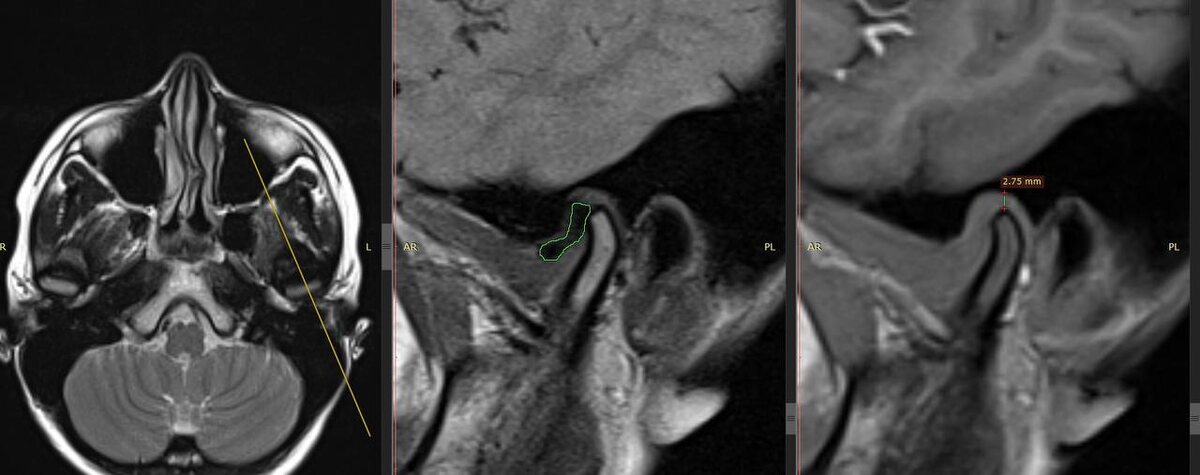

фото 1 - дистальное смещение суставной головки и неполная вентральная дислокация суставного диска с репозицией

По МРТ исследованию (фото 1) мы видим дистальное смещение суставной головки и неполную вентральную дислокацию суставного диска с репозицией.

Через 1,5 месяца - отсутствие жалоб, повторное МРТ исследование - центрированное положение суставной головки, суставной диск на 12 часах условного циферблата. Пациент передан на дальнейшее ортодонтическое лечение.